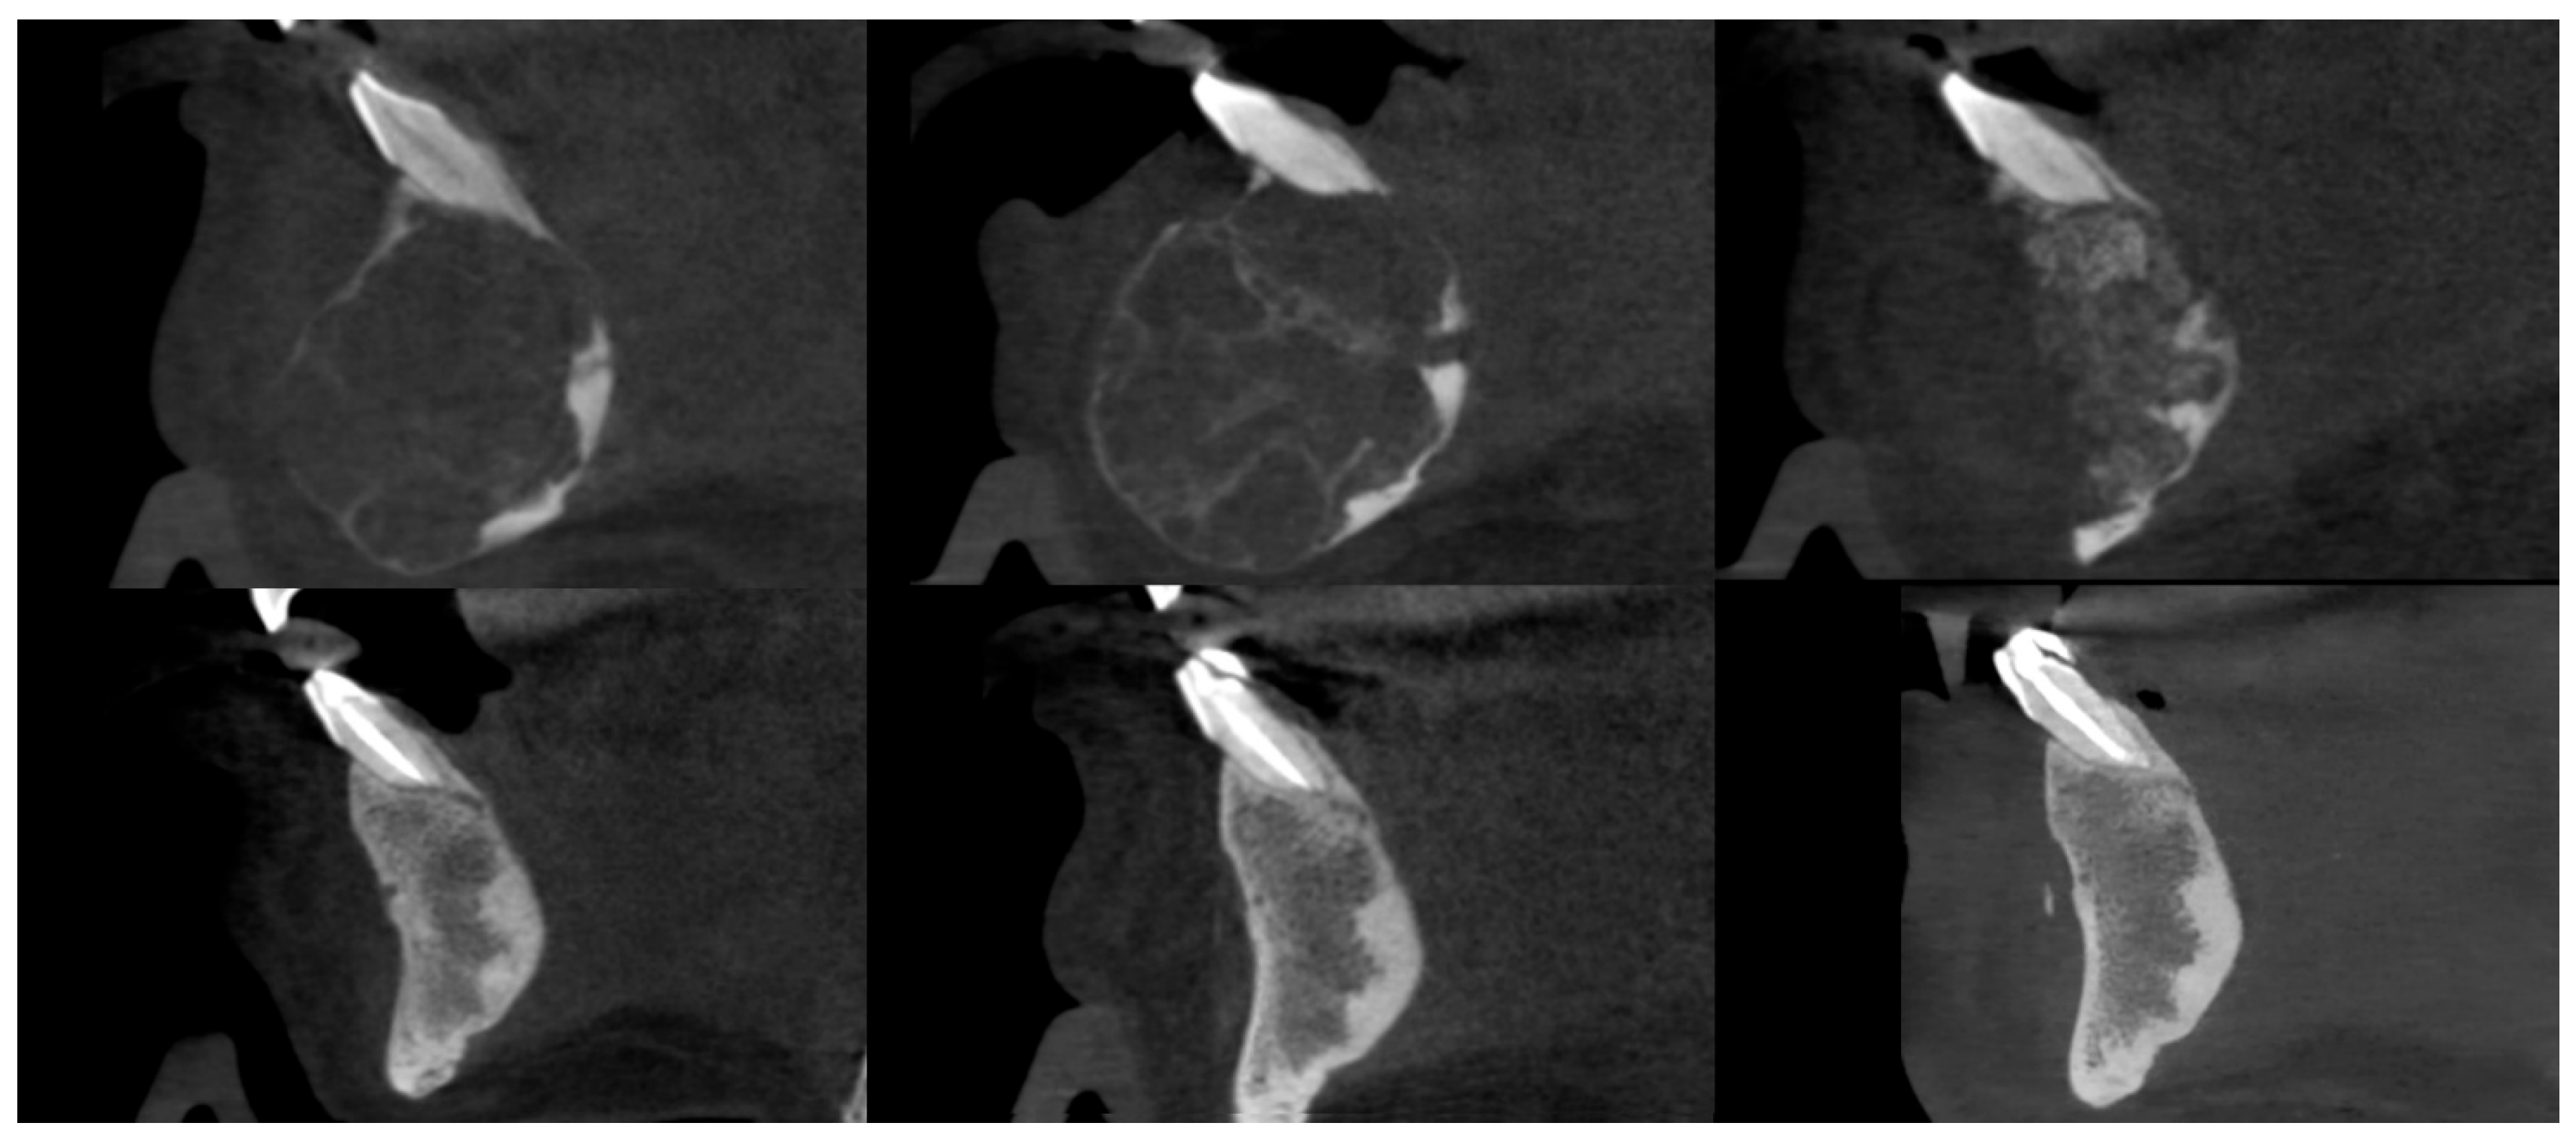

3.3. Osteosclerotic Rim (Peripheral Corticalization)

3.4. Complications During Treatment

3.5. Recurrence

4. Discussion